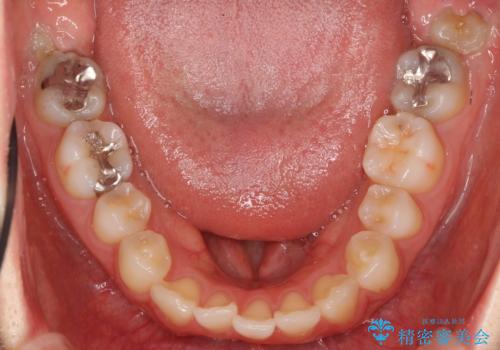

下の前歯が生まれつき3本でした。

下を3本でそのまま並べてあるため、上下の正中は合いません。

合わせようとすると抜歯か、下の隙間を無理やり開けてブリッジとなりますが、そこまでするメリットがないため、下はそのままの歯の数を生かしています。